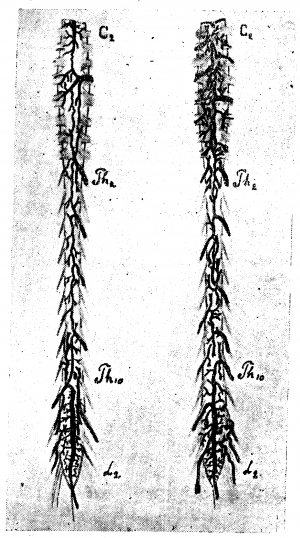

Вены вещества спинного мозга (рис. 1). Центральные вены, подобно артериям, бывают правые и левые, то есть выносят кровь из (какой-либо одной половины серого вещества. В отличие от соответствующих артерий, они анастомозируюг между собой. Возникают они из мелких веточек, близких по калибру к артериолам, и сами являются очень мелкими тканевыми сосудиками. Поллак отмечает, что в сером веществе спинного мозга очень редко встречаются относительно более крупные венозные сосуды: мелкие веточки почти непосредственно собираются, в относительно крупный стволик центральной вены. Центральные вены впадают в передние венозные тракты или вернее они образуют их. Вены белого вещества спинного мозга крупнее соответствующих артериол и центральных вен (вен серого вещества). В отличие от артерий вены серого и белого вещества богато анастомозируют между собой, так что кровь из серого вещества может изливаться двумя путям: через передние и через боковые и задние тракты, чем и объясняется относительно малый калибр вен серого вещества и кажущееся нарушение правила о превосходстве площади сечения вен над площадью сечения соответствующих артерий.

Вены поверхности спинного мозга (рис. 2). Вены мягкой мозговой оболочки, как и артерии, расположены преимущественно продольно, но число венозных стволов гораздо менее постоянно, чем артериальных. Даже на одном препарате на разных уровнях оно различно. Вены змеятся вдоль спинного мозга, иногда сплетаясь в «нераспутываемый клубок», как выражается Адамкевич. Строго говоря, на поверхности спинного мозга существует настоящее венозное сплетение, аналогичное сплетениям позвоночного канала. Число, калибр и расположение отдельных стволов венозного сплетения спинного мозга подлежат очень большим колебаниям.

Мы уже неоднократно упоминали о работе Словохотова, исследовавшего развитие сосудов спинного мозга в эмбриональный период и показавшего, что закладка сосудов в эмбрионах проходит по эмбриональному типу, который ещё ясно выражен до 6-го лунного месяца. Во вторую половину утробной жизни происходит перестройка метамерного типа на стволовой (рис. 3 и 17).

По нашим исследованиям, у новорожденных строение вен спинного мозга уже приобретает все основные характерные черты, свойственные взрослому; мы можем совершенно определённо констатировать наличие продольных стволов, вены корешков выражены ясно, неравномерны по калибру и неравномерно распределяются.

В возрасте 4—5 месяцев внеутробной жизни, мы видели уже богато развитую поверхностную венозную сеть, но она ещё очень тонка, почти капиллярна. Передний средний венозный тракт вполне сформирован; боковые тракты намечаются на нашем препарате спереди, в грудном отделе спинного мозга. Вены спинно-мозговых корешков выражены хорошо, но ещё сохраняют эмбриональный тип в том отношении, что вены главных оттоков (корешков шейного и поясничного утолщения) ещё не так резко преобладают над другими корешковыми венами, как это бывает у взрослых.

Большая вена Адамкевича типично отходит от среднего переднего венозного тракта, очень хорошо развитого.

Задняя поверхность мозга на том же препарате представляет более пёструю картину: шейная часть задней поверхности покрыта тончайшей сетью вен, но продольное расположение сосудов по корешкам и задней расщелине уже намечается. Грудная часть препарата особенно интересна: с 8-м шейным корешком отходит (типично) вена спинно-мозгового нерва; сверху она соединена с венозными стволиками шейной сети, а книзу проходит в виде крайне извитого, часто пересекающего медиальную линию сосуда. Вены некоторых корешков (например, 2, 4 грудного) начинаются двумя корнями — верхним и нижним, так что намечается боковой тракт. Средний венозный тракт выравнивается в грудной области и змеится вдоль средней линии, причём на протяжении 6—7 грудных сегментов его сопровождает параллельный, уже хорошо сформированный стволик, спускающийся вдоль входа в мозг задних корешков. Оттоки в поясничной области развиты хорошо на 12-м грудном справа и на 1—2-м поясничных корешках слева.

Форма первая. Рис. 6, 7, 8 дают примеры первого типа.

На передней поверхности препарата, изображенного на рис. 6, можно отметить неравномерность калибра среднего ствола, склонность к образованию островков, но, в общем, тракт можно довольно легко проследить на всём его протяжении. На рис. 7 задержка редукции выражена больше: калибр переднего тракта очень мелок, тракт почти прерывается, отклоняясь несколько в сторону; боковые же тракты выражены относительно лучше. Гораздо больше выражена задержка редукции на препарате, изображённом на рис. 8. В нижней части шейного отдела и в грудном отделе средний тракт только отгадывается в системе продольных петель, с частыми боковыми оттоками (ср. верхнюю грудную область, особенно 3-й грудной сегмент, где средний тракт совершенно отходит в сторону, прерывается и оба его отрезка впадают отдельно в параллельные венозные стволики третьего грудного корешка). В области 12-го грудного—1-го поясничного сегмента тракт также отклоняется в сторону, образует островок и почти истощается. В грудной области тракт распадается на два слабых извилистых рукава, образующих длинный островок, а в области 8—11-го сегмента видны даже три параллельных стволика. Оттоки рассеяны, мелки, на одном корешке зачастую видны 2—3 венки. Вена Адамкевича выражена слабо (1 крестцовый корешок слева); боковые тракты едва намечаются прерывистой линией. Эту картину можно считать типичной задержкой редукции, наиболее выраженной для передней венозной сети в ряду изученных нами препаратов.

На рис. 9 видна неравномерность калибра переднего тракта, его извитость, рассеянность оттоков; на рис. 10 видны те же черты: тракт прерывается, извит, образует островки, во многих местах существуют довольно значительные параллельные стволы. Этот рисунок заслуживает внимания: на изображённом здесь препарате задержка редукции выражена и спереди и сзади, а вместе с тем венозные стволы поверхностной сети широки, налиты кровью и при невнимательном взгляде препарат легко отнести к магистральному типу, что было бы, конечно, ошибочно. Развитость стволов, набухлость вен в данном случае являются следствием возрастного изменения и нарушения венозного кровообращения у сердечнобольного (см. ниже гл. IV, болезни сердца).

Задняя поверхность препаратов, изображённых на рис. 6, 7, 8, 10, 11 представляет ещё более резкую картину задержки редукции первичной венозной сети. Так, на рис. 10, несмотря на резкую набухлость вен, в шейной и верхней грудной области почти не выражены продольные стволы: это еще ясней видно на рис. 11, где местами продольные стволы совсем не видны, местами же они только намечаются. Изображённый на рисунке препарат представляет большой интерес с патологической точки зрения и к нему мы вернёмся в гл. IV.

Очень типична картина задержки редукции первичной венозной сети задней поверхности, видная на рис. 7. Мы отмечаем резкую неравномерность калибра и плохое развитие среднего тракта, отклонение от средней линии, перерыв на уровне 7-го — 11-го грудного сегмента, плохую выраженность продольных стволов, местами трудно выделяемых из венозной сети, рассеянность оттоков. Аналогичная картина видна и на рис. 8.

Вторая форма. Магистральный тип поверхностных вен спинного мозга характеризуется двумя основными чертами: хорошей выраженностью среднего тракта и хорошей централизацией оттоков. Боковые продольные тракты обычно только намечаются и, повидимому, вообще редуцируются (рис. 12, 13, 14).

На рис. 12 довольно хорошо выражен магистральный тип вен передней поверхности, строение же вен задней поверхности является переходным. Лучше магистральный тип выражен на обеих поверхностях препарата, изображённого на рис. 13, где почти не видны боковые тракты, а средние тракты представляются хорошо развитыми, относительно равномерными по калибру, оттоки хорошо централизованы. На рис. 14, 15, 16, 17 и 18 можно видеть различные переходные вариации.